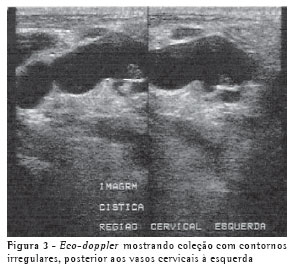

RELATO DO CASOUma mulher de 63 anos, do lar, não tabagista, previamente hígida, apresentou-se com queixa de aumento de volume em pescoço, face anterior do tórax, abdome e membros inferiores. Havia associação com dispnéia discreta aos esforços. O quadro teve início após atividade física leve em academia de ginástica, havia cinco dias. Negava doença pulmonar prévia e referia uso de fluoxetina a 20 mg/dia, bromazepam a 3 mg/dia e reposição hormonal feminina regular. Ao exame clínico observou-se um discreto aumento de volume em fossa supraclavicular esquerda e face lateral direita do pescoço. Observou-se ainda diminuição do murmúrio vesicular de forma difusa e de frêmito toracovocal em bases (direito maior que esquerdo), além de edema de parede abdominal anterior e de membros inferiores (grau I/IV). Foram solicitados hemograma, coagulograma, glicemia, creatinina, uréia, velocidade de hemossedimentação, colesterol total, HDL, triglicerídeos, T3, T4, TSH e parcial de urina, os quais se apresentaram todos normais, descartando a presença de dislipidemia, coagulopatia, infecção, nefropatia e hipotireoidismo. A avaliação radiológica do tórax revelou um pequeno derrame pleural bilateral (Figura 1), confirmado pela tomografia axial computadorizada de tórax (Figura 2A). Esta foi complementada com cortes ao nível do pescoço, que evidenciaram edema na região supraclavicular esquerda com imagem hipodensa (20 x 10 mm) adjacente ao feixe vasculonervoso do pescoço (Figura 2B). A ultra-sonografia da região cervical mostrou a formação de uma coleção cística, posteriormente aos vasos cervicais, sugestiva da ruptura do tronco jugular esquerdo. Demonstrou ainda um pequeno aumento da espessura do músculo esternocleidomastóideo esquerdo, sugestivo de processo inflamatório secundário a distensão muscular (Figura 3). A paciente foi submetida a toracocentese diagnóstica à direita com obtenção de líquido leitoso compatível com QT. A análise laboratorial demonstrou tratar-se de um exsudato com predomínio de polimorfonucleares e com dosagem de triglicerídeos de 2.035 mg/dl, colesterol de 131 mg/dl e proteínas de 9,7 g/dl, confirmando o quadro laboratorial de QT. Foram realizadas citologia oncótica, bacterioscopia de Ziehl, micológico direto e culturas, que resultaram negativos, descartando processos malignos e doenças infecciosas.